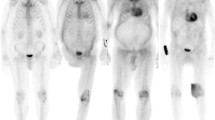

Myocardial (top 2 rows) and systemic organ (bottom row) uptake of 18F-florbetapir and 124I-evuzamitide in patients with various forms of amyloidosis. Liver uptake is physiologic with 18F-florbetapir imaging. Amyloid PET tracers bind to various types of amyloid fibrils and can image amyloid deposition in the cardiac and extracardiac tissues. Apo-A-IV = Apolipoprotein AIV. (Reprinted with permission from Dorbala et al. [11].)